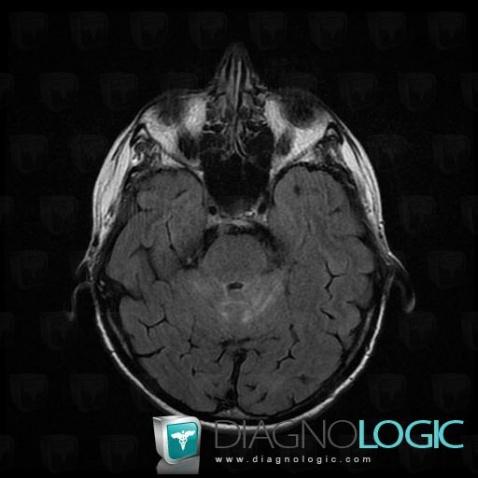

Les images ci-dessous illustrent ce dossier pour les diagnostics Carcinose méningée, Méningite carcinomateuse, pour les modalités (IRM)

Voici les informations spécifiques à l'image clé ci dessus:

- Diagnostic Méningite carcinomateuse, Localisation(s) Région cortico sous corticale, comportant les gammes Lésion sous corticale